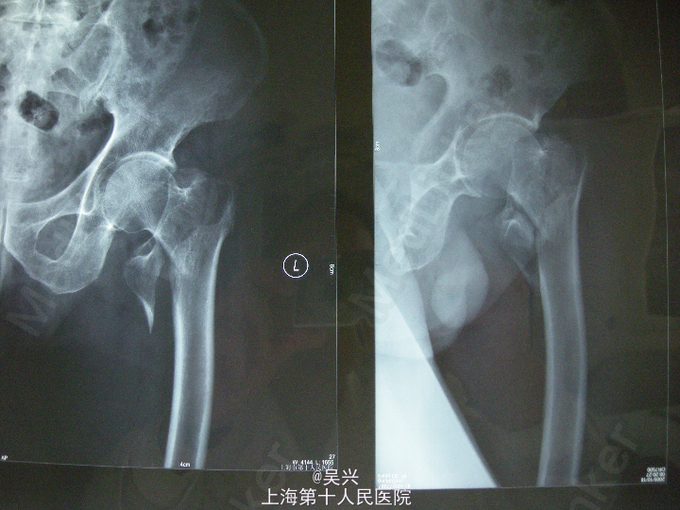

左髋跌伤3小时急症入院

查体,左髋肿胀、触痛、活动受限,左足外旋畸形。 辅查:X线左股骨粗隆间骨折,移位。

诊断:左股骨粗隆间骨折 处理:入院后予患肢皮肤牵引,完善术前准备,第3天行左股骨粗隆间骨折闭合复位、PFN-a内固定术。